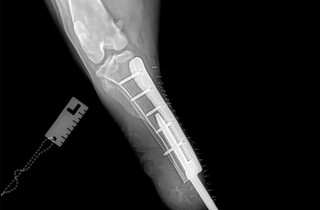

У Харкові вперше поставили біоінтегрований протез собаці, якого скалічили росіяни. Допоміг тварині хірург-ветеринар Віталій Клубань та його колеги. Він повідомив у Facebook про здійснення вдалої операції на базі Салтівської ветеринарної клініки.

56-кілограмовий чорний тер'єр потрапив під касетний обстріл росіян біля дитячого садочка в Харківській області та втратив лапу.

Лікарі провели собаці надскладну операцію та вживили біоінтегрований протез.

Наразі тер'єр вже встиг звикнути до «нової» кінцівки та вправно бігає.